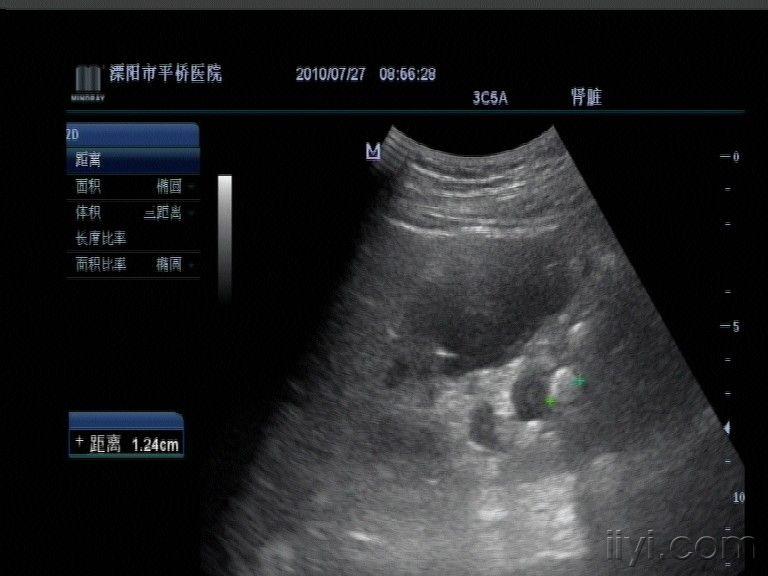

(图) ,4 肾结石声像图

图片尺寸1085x800